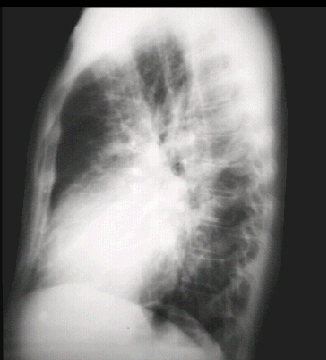

Lateral view

The lateral view shows left ventricular enlargement, as evidenced by posterior displacement of the left ventricular shadow. Note the increased vascular markings in the lung fields.